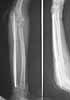

This patient,a middle aged malewas a diagnosed case of hypophosphatemic osteomalacia on treatment. Unfortunately he discontinued treatment since he was poor and also neutral phosphate was not available locally. He presented with pathological fracture of left femur and a failing neck of same femur.

We managed to get neutral phosphate, initiated medical treatment and did an antegrade SIGN nailing of left femur along with couple of screws to neck using miss a nail technique. He complained of pain of the right femur and both forearms. In OT these areas were screened using image intensifier and found that he has looser zones of all these with impending fractures. Yesterday we did a retrograde nailing of right femur usingSIGN nail. Both ulnas were stabilised usingLambrudini wires in a closed fashion. All fractures and looser zones were stabilised by closed surgery using image intensifier. It may be interesting to see the post of picture of both the hips in which one side shows an antegrade femoral SIGN nail and the other side shows a retrograde SIGN nail.